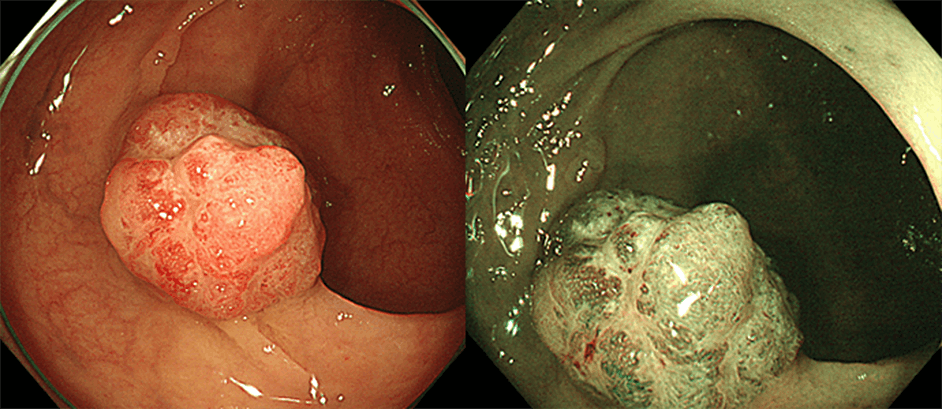

進行大腸がん(右はNBI観察像)

この病変のNBI併用拡大観察では、無構造領域内の大腸がんの多くは、良性腫瘍である腺腫が悪性化してがんとなったものです。この腺腫が悪性化してがんになるという経路を、adenoma-carcinoma sequenceといいます。